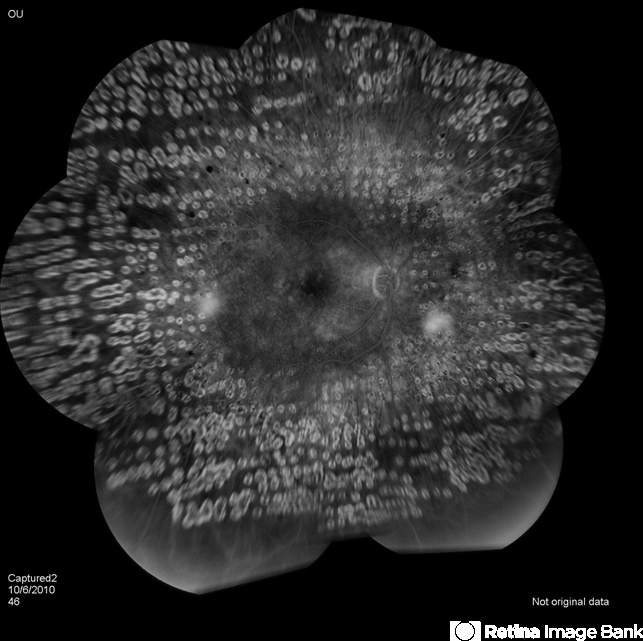

Excellent montage of this right eye with proliferative disease and extensive PRP laser. These are not easily captured and these are very well illuminated.

- pan-retinal photocoagulation (PRP), neovascularization (NV)

- Extensive pan-retinal photocoagulation.